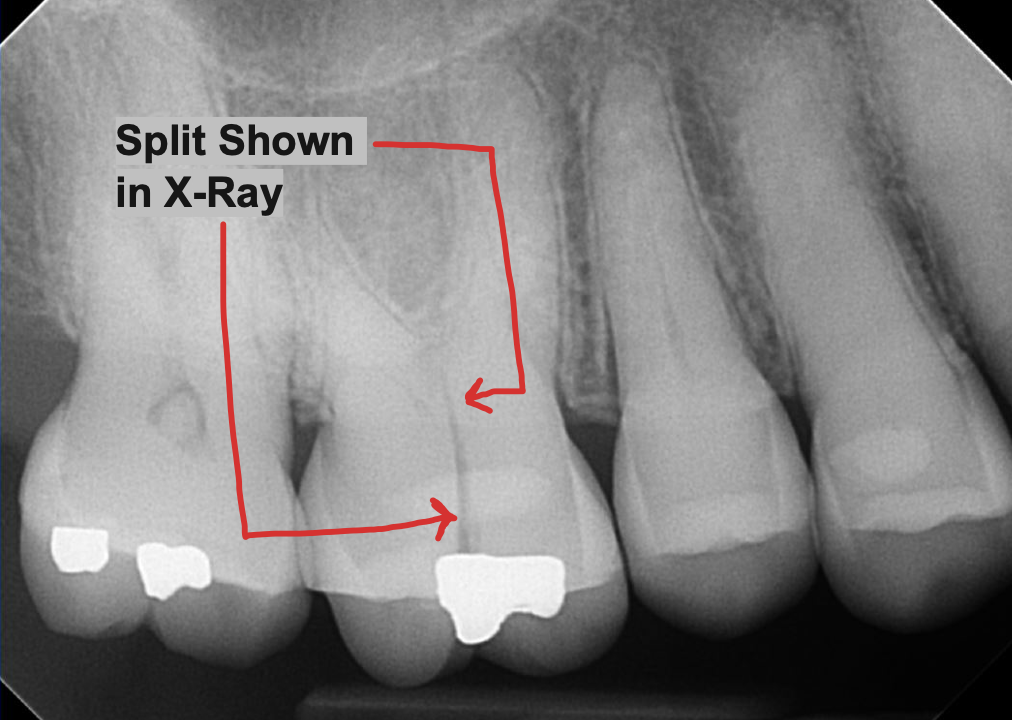

👀 Step 1: Pre-Op Evaluation

Before removing the tooth, we assessed bone health and root position with detailed imaging. In this case, the tooth had a prior root canal and a cavity on the back side, which caused the crown to loosen and eventually fall off. This tooth could not be saved by a new crown, so it needed to be extracted to prevent risk of infection and further damage of surrounding tissue. After reviewing alternative options, this patient is planning on a future dental implant to restore the site.

Images:

X Ray of tooth #18 Prior to Extraction

✅ Purpose: understand root formation, nerve anatomy, and ensure the socket walls are intact for grafting.